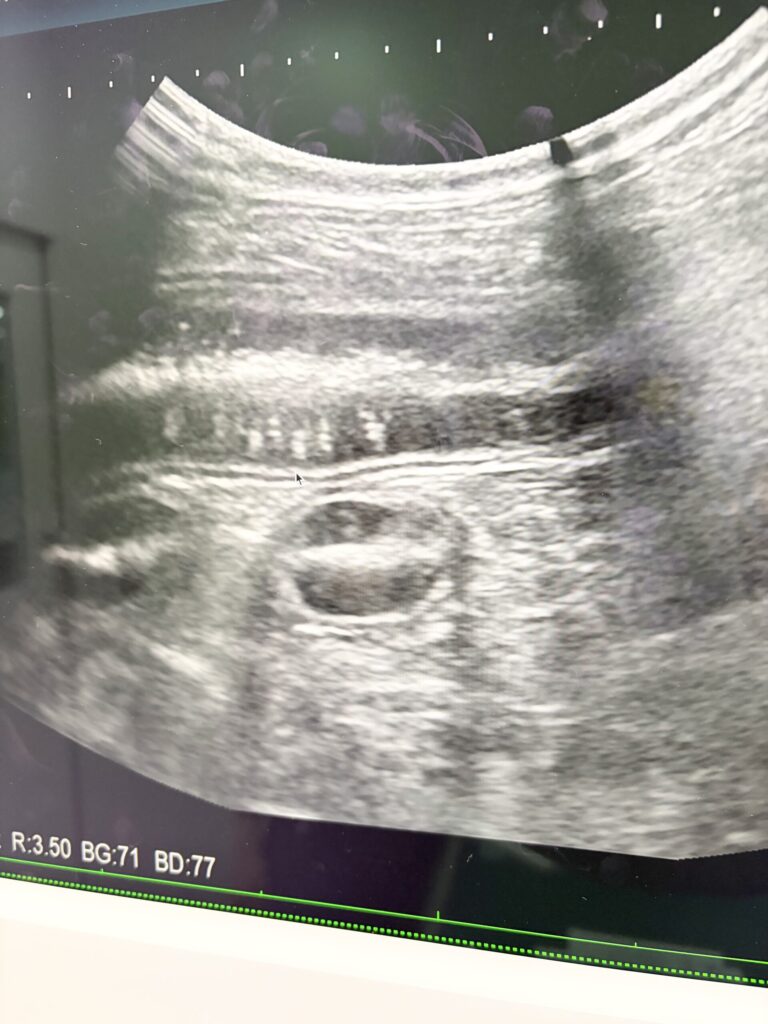

エコー検査、便検査をしてもらい

急性胃腸炎だって、元気だし食欲もあるからおクスリ飲んで数日で治るでしょうって